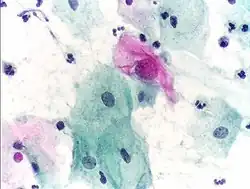

Micrograph of a Pap test showing trichomoniasis. Trichomonas organism seen in the upper right. Pap stain. -

Infestation by Trichomonas vaginalis